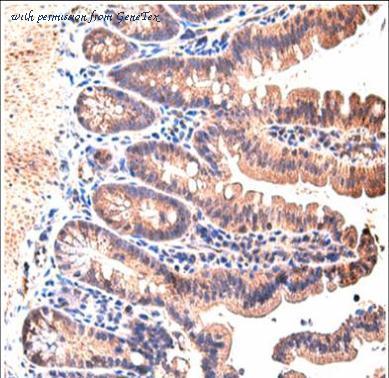

- Stat3 anticorps